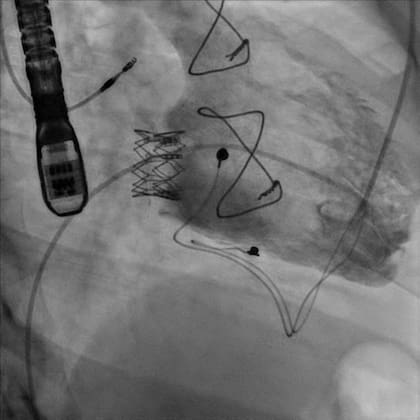

Ahora, en un procedimiento pionero, un equipo de la Fundación Favaloro encabezado por el doctor Oscar Méndiz realizó por primera vez en el país el reemplazo por cateterismo de la última válvula cardíaca que faltaba reparar con esta técnica, la tricúspide, que separa el ventrículo derecho de la aurícula del mismo lado.

Igual que en las demás, para reparar la "tricúspide" se procede a una sedación consciente, se realiza una punción con sutura percutánea (sin cortar) y, luego de cruzar la válvula, se avanza la prótesis montada sobre un catéter dirigible que contiene un balón. Al inflarlo, éste expande la válvula de pericardio bovino, que queda sostenida por un stent gigante.